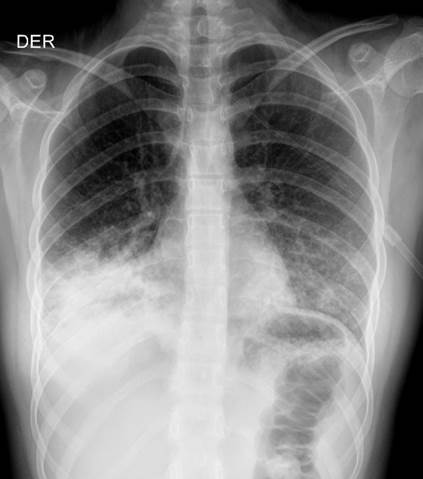

Se trasladan al servicio de urgencias pediatría femenina de 55 kg de peso, talla de 150 cm, a la inspección somnolienta, con taquicardia, taquipnea, normo tensa (114/63 mmhg), paraclínicos iniciales donde se evidencia leucocitosis, disminución de 4 gr de hemoglobina con respecto a los tomados ambulatoriamente, radiografía de tórax (ver figura 1), gases arteriales con acidosis metabólica hiperlactatemia, resto de paraclínicos iniciales en rangos de normalidad.

Figura 1. Infiltrado intersticial de distribución. Infiltrado intersticial de distribución para hiliar y basal derecho, la silueta cardiaca y aorta son de tamaño y configuración normales. Tráquea central. Mediastino normal. Estructuras óseas y tejidos blandos normales.